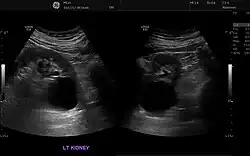

Ecografía renal

Se utiliza para obtener imágenes de los riñones, los uréteres y la vejiga. Se realiza este examen cuando los médicos sospechan de alguna problema renal y este les permite identificar:

- el tamaño de los riñones

- lesiones

- anomalías presentes desde el nacimiento

- obstrucciones o piedras en los riñones

- complicaciones por infección en el tracto urinario

- quistes o tumores[19]